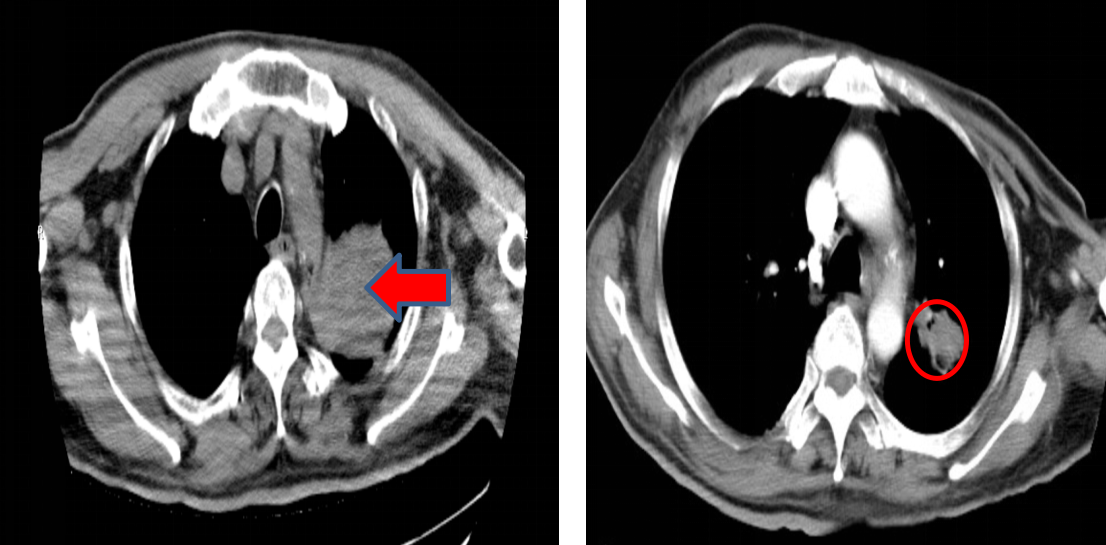

• 影像学检查(2022年9月): PET-CT提示左肺上叶尖后段中央型肺癌可能性大,伴纵膈、左肺门淋巴结及多处骨骼、肝脏转移可能。胸部CT显示左肺上叶团块状软组织影,伴左侧第3前肋溶骨性骨质破坏。头颅MRI未见明确颅内转移。

图片7.png

胸部CT基线(2022年9月)

• 病理学检查(2022年9月): CT引导下经皮肺穿刺活检病理符合鳞状细胞癌。免疫组化结果:CK5/6 (+),P40 (+),CK7 (-),TTF-1 (-),Syn (-),Ki67 (60%+),CD56 (-),LCA (-),Napsin A (-),P63 (+),CK (+)。

胸部CT(2022年11月):1、左肺上叶团块状软组织密度影并左肺上叶阻塞性炎症,左侧第3前肋骨质破坏,考虑肺癌,肿块较前减小,炎症较前吸收。2、纵隔及左侧肺门区多发淋巴结稍增大,部分钙化。完成2个周期治疗后,疗效评价为PR,随后继续该方案治疗2周期。

图片8.png

胸部CT(左:基线;右:2022年11月)